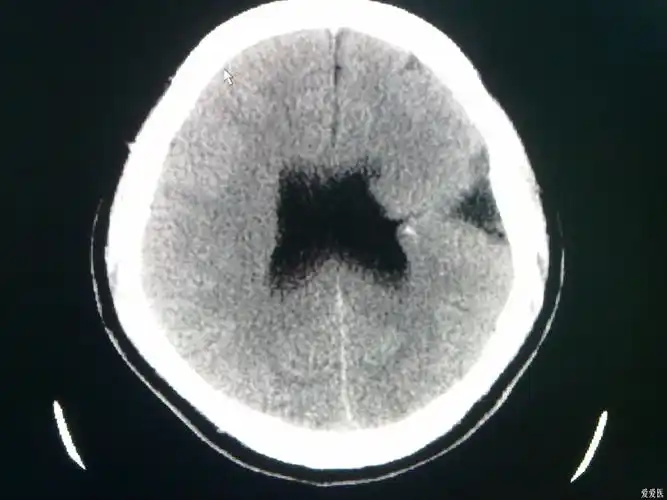

今天做到的病例脑裂畸形